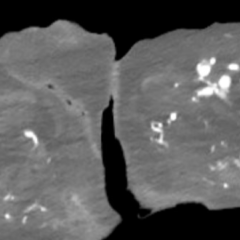

This case report discusses a 36-year-old male who presented to the emergency department with an atypical story for acute coronary syndrome (ACS). Initially, the patient was felt to have a non-diagnostic electrocardiogram (ECG). Once the laboratory test results were obtained and the initial high-sensitivity troponin was noted to be elevated, the initial ECG was again reviewed. The patient was felt this time to have an abnormal ECG, demonstrating borderline ST elevation in leads I, aVL, and V2-V5. The interventional cardiologist on call was contacted, and the cardiac catheterization lab was activated. Upon left heart catheterization, the patient was found to have a spontaneous coronary artery dissection (SCAD) of the distal left anterior descending (LAD) artery. Post-catheterization, the patient was observed on cardiac telemetry and started on dual antiplatelet therapy. Echocardiogram revealed a preserved ejection fraction (EF), but hypokinesis of the apical anterior, anterolateral, inferior, and apical myocardium. The patient was discharged within 48 hours without any complications.